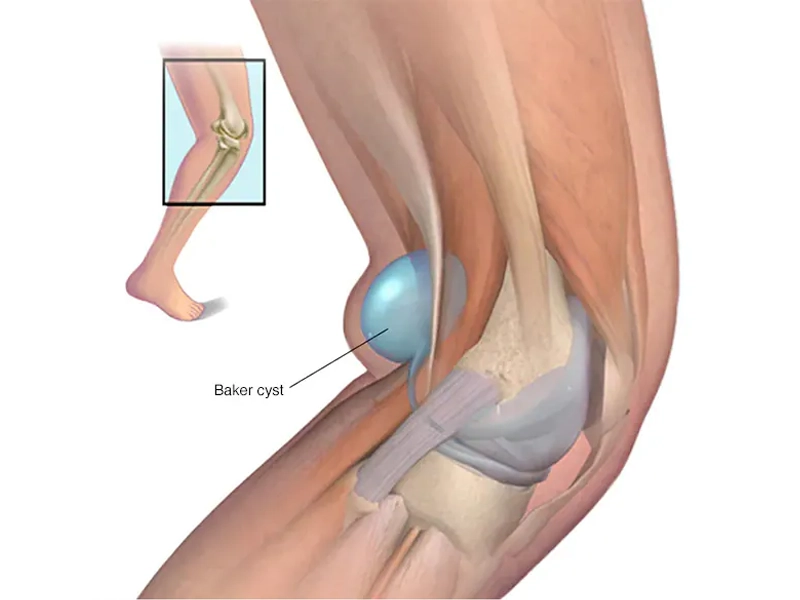

کیست بیکر زانو (Baker’s cyst) یا کیست پوپلیتئال، به تجمع مایع مفصلی در پشت زانو گفته میشود که معمولاً به شکل یک برجستگی یا تورم نمایان میشود. این وضعیت اغلب ناشی از یک مشکل زمینهای مانند التهاب، پارگی منیسک یا آرتروز است. نام این کیست از دکتر ویلیام بیکر، جراح انگلیسی قرن نوزدهم گرفته شده […]